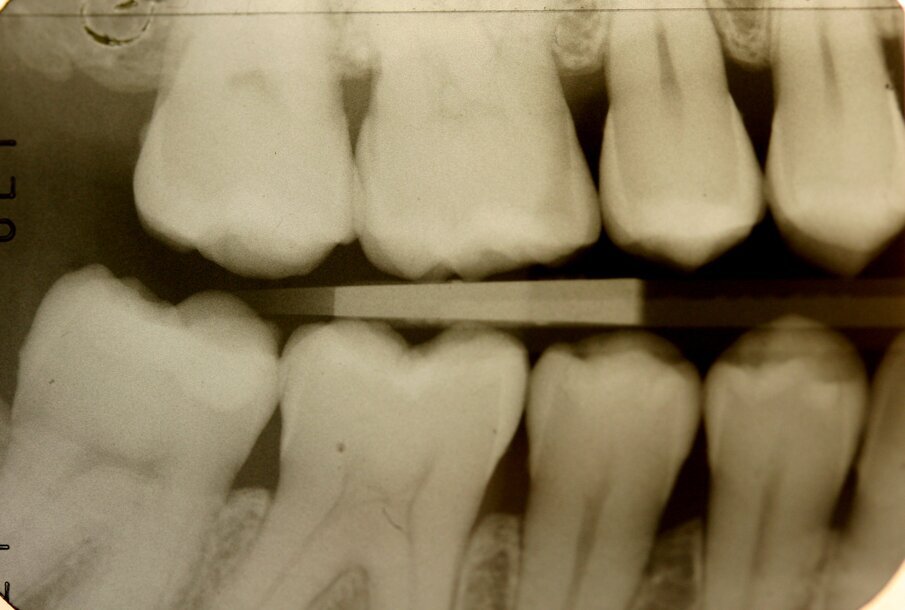

La paziente, FF di anni 38, è giunta alla mia osservazione per la cura delle lesioni cariose presenti. All’esame obiettivo non erano evidenti lesioni cariose di notevole entità (Figg. 1, 2): solo attraverso le bite-wing (Figg. 3, 4), mezzo indispensabile per la diagnosi odontoiatrica in conservativa, si evince la presenza di numerose lesioni cariose coinvolgenti il tessuto dentinale. La paziente richiedeva il raggiungimento di un risultato estetico ottimale, ovvero la mimetizzazione del materiale composito con il tessuto smalteo; oltre a questa esigenza si doveva unire quella di effettuare una riabilitazione funzionale ovvero, trattandosi del settore posteriore, che sopportasse il carico masticatorio garantendo la minima usura possibile nel tempo. Alla paziente è stato proposto un piano di trattamento che prevedeva la cura diretta delle lesioni cariose suddivise per quadranti e la riabilitazione indiretta dell’elemento 47 in modo da permettere la migliore precisione marginale garantendo un ottimo follow-up a lungo termine. Si è proceduto con la riabilitazione mediante il composito di recente introduzione Enamel Plus HRi Bio Function (Micerium, Avegno, Genova). Bio Function è disponibile in 3 smalti: BF1 basso valore - BF2 medio valore - BF3 alto valore e in 9 dentine: BD0 - BD0,5 (per restauri di denti particolarmente bianchi o sbiancati) BD1 (A1 Scala Vita) - BD2 (A2 Scala Vita) - BD3 (A3 Scala Vita) - BD3,5 (A3,5 Scala Vita) - BD4 (A4 Scala Vita) BD5 - BD6.

Fig. 3_Bite-wing di destra.

Fig. 4_Bite-wing di sinistra.